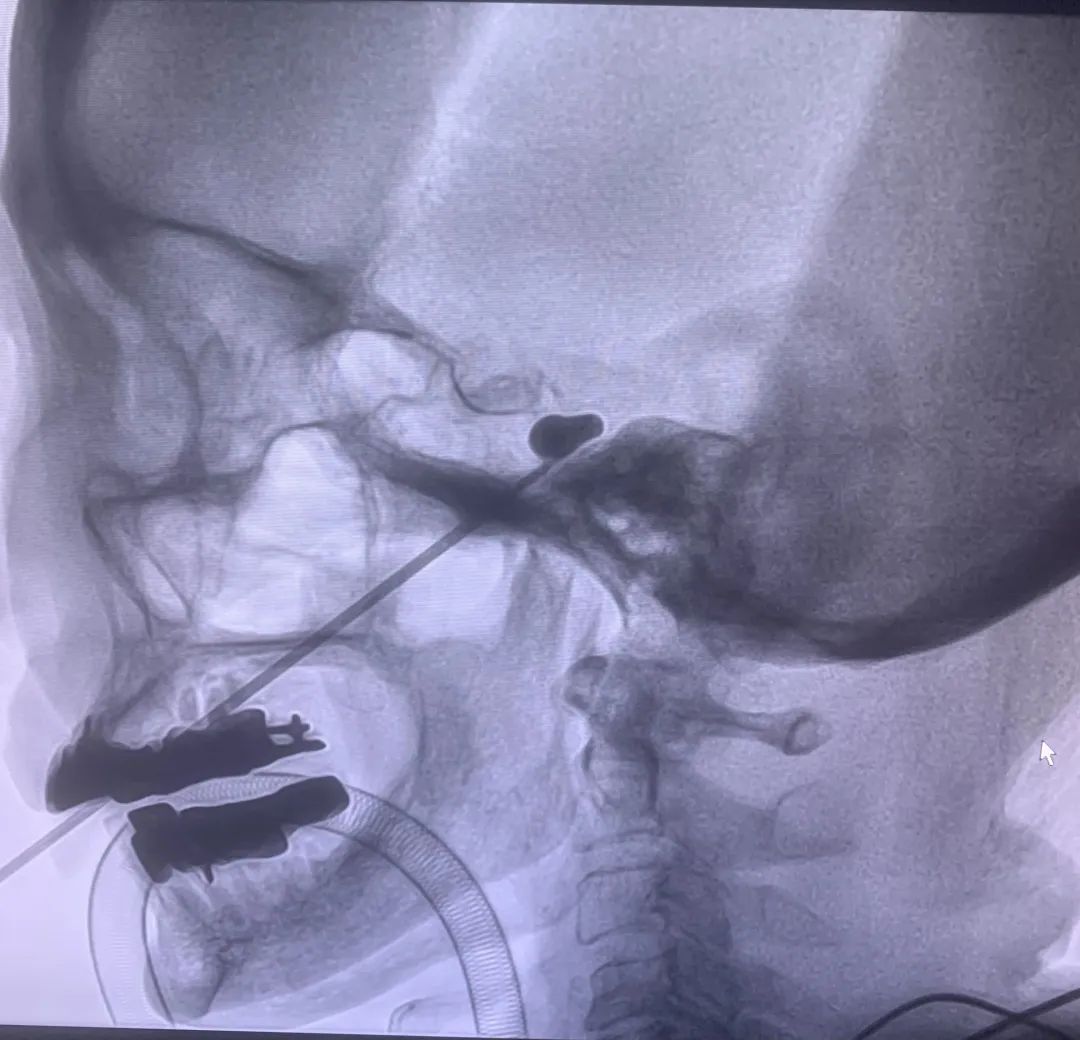

PBC 是在影像介入下经面部皮肤表面用一跟细针穿刺通过卵圆孔,将微球囊导管置入 Meckel’s 囊,压迫三叉神经神经半月节来治疗三叉神经痛。

龙岗区人民医院疼痛科团队给苏奶奶来的这「一针」,正是 PBC。

学科团队根据苏奶奶的病情和高龄情况、科室业务技术能力等综合研判,决定采用经皮三叉神经半月结球囊压迫术解决她的病痛。

完善相关检查和手术前准备后,90 岁的苏奶奶在麻醉科和介入室护理团队的保驾护航下,接受了全麻微创手术。

手术中生命体征平稳,麻醉复苏后她的疼痛消失,仅是左侧颜面部留下一个非常小的针孔和轻微的麻木感。